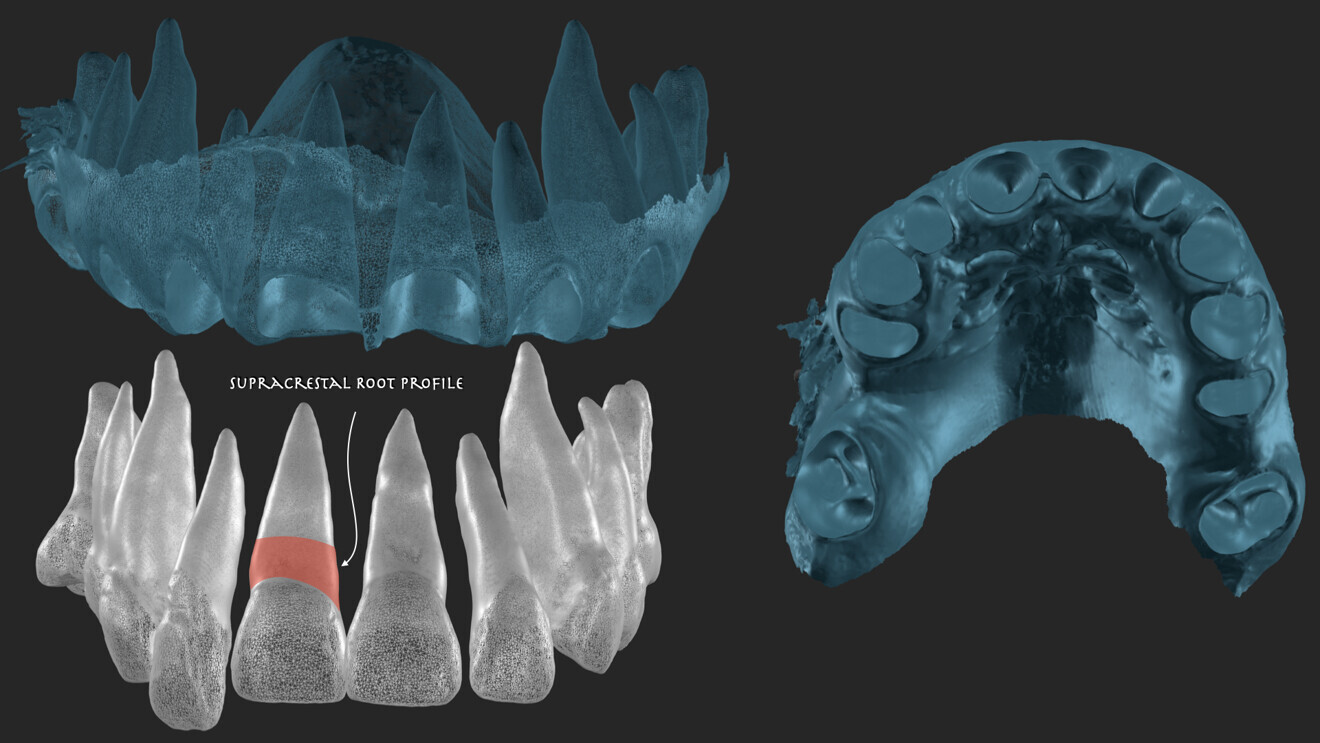

For effective 3D planning, having a combined extraction model is essential. This provides the dental technician with clear reference points for creating custom support that follows the emergence profile of each individual tooth (Figs. 6 & 7).

Fig. 6: Combination of the CBCT and the intra-oral scans for segmentation.

Fig. 7: Combined extraction model.